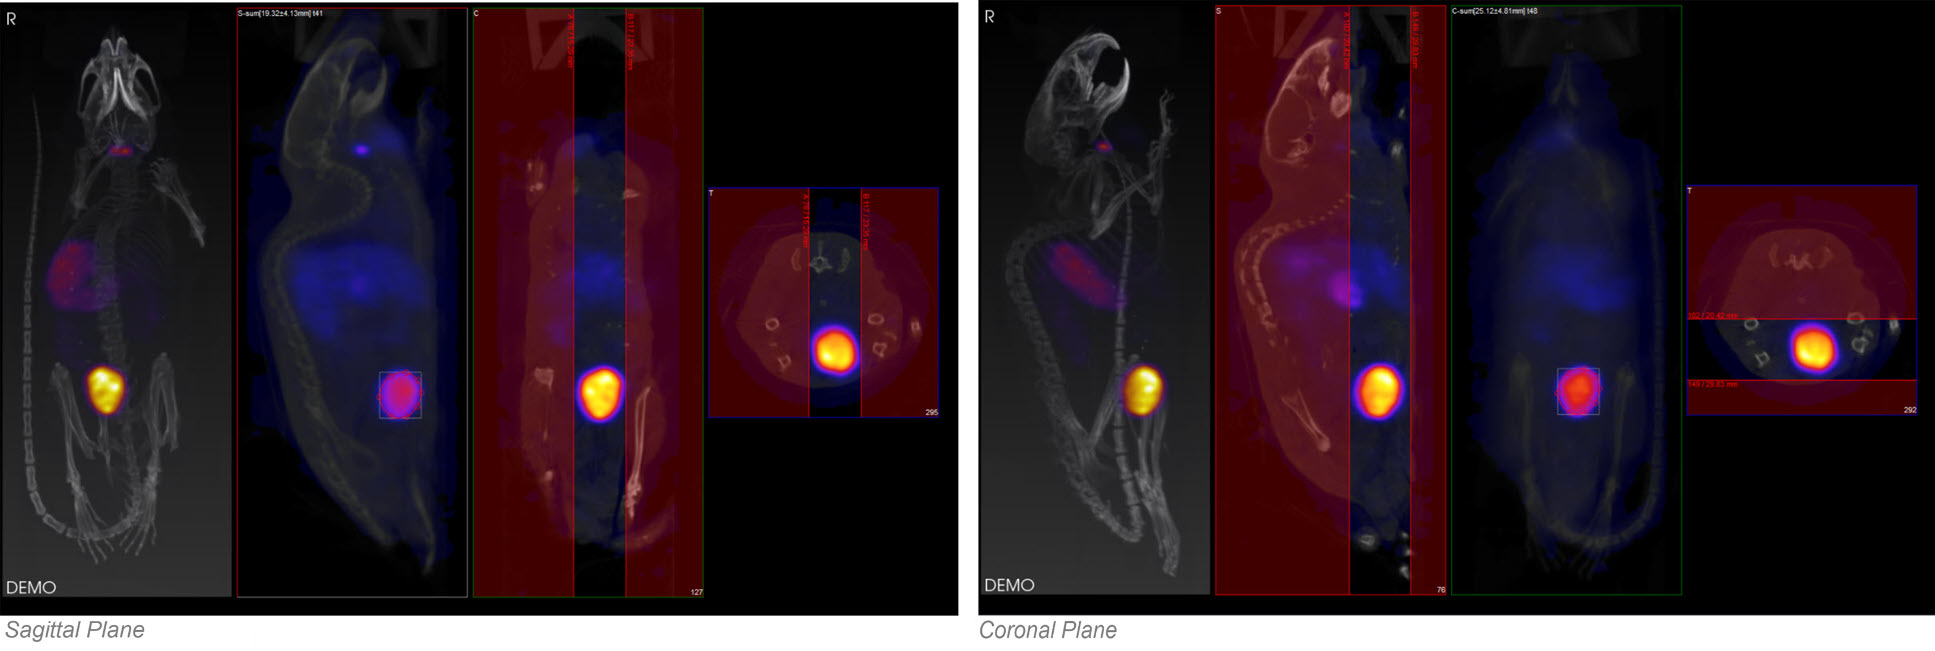

The ROI may be drawn in either the transverse (default), coronal, or sagittal plane. To toggle between these options, use the View menu in the Operator tab of the main menu.

In this example, using the default settings, the axial sliders determine the extent of the ROI in the axial direction. The region or pre-defined shape described below determines the bounds of the ROI in the transverse plane.

By using the View menu, it is also possible to draw ROI boundaries in the sagittal plane or coronal plane: